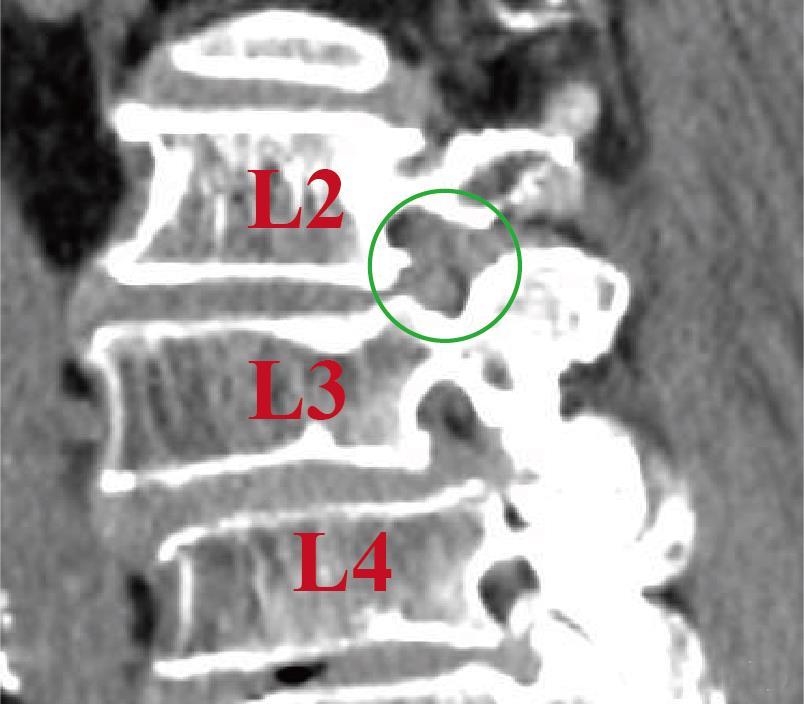

• 单通道非同轴脊柱内镜经椎间孔外入路(椎板外切迹)治疗极外侧椎间盘突出症的临床疗效观察

摘要:目的 观察单通道非同轴脊柱内镜经椎间孔外入路(椎板外切迹)治疗极外侧椎间盘突出症(FLLDH)的临床疗效。方法 回顾性分析2022年5月-2024年5月该院收治的,行单通道非同轴脊柱内镜经椎间孔外入路(椎板外切迹)治疗的FLLDH患者70例。于术前和术后,评估腰腿疼痛程度、腰椎功能和临床疗效。结果 相较于术前,术后3 d和3个月,患者下肢视觉模拟评分法(VAS)评分、腰部VAS评分、Oswestry功能障碍指数(ODI)、数字分级评分法(NRS)评分和Roland-Morris功能障碍问卷(RMDQ)评分明显降低,日本骨科协会(JOA)评分明显升高,差异均有统计学意义(P < 0.05);改良MacNab评分标准显示,末次随访时的优良率为94.28%。结论 单通道非同轴脊柱内镜经椎间孔外入路(椎板外切迹)治疗FLLDH,能明显改善患者腰腿疼痛和腰椎下肢功能,其具有创伤小、易操作、安全性高和疗效好等优点,值得在临床推广应用。